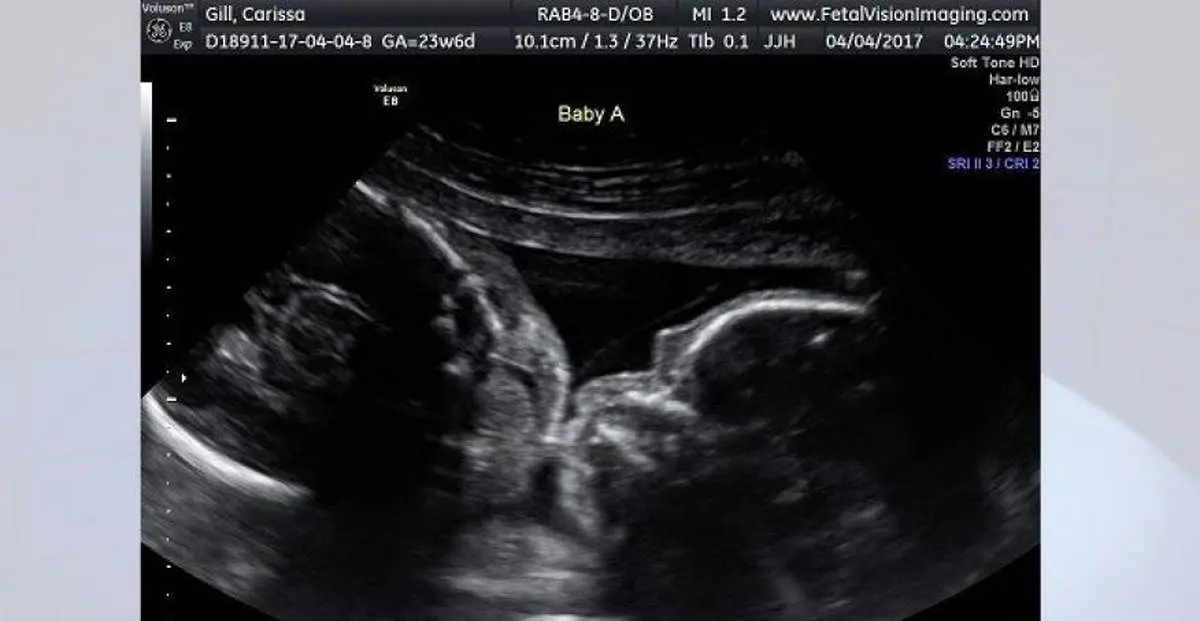

عجیبترین سونوگرافی تاریخ/ دوقلوهایی که درحال بوسیدن هم دیده شدند +عکس

وقتی نوبت به سونوگرافی کاریسا در این مرکز تصویربرداری از جنین رسید، این زوج، شاهد صحنهای غیر عادی بودند. دوقلوهای یکسان آنها، ایزابل و کالی، یکدیگر را در آغوش گرفته بودند و به نظر میآمد که در حال بوسیدن همدیگر هستند.

کاریسا در مصاحبه با «فاکس 29»، گفت: من دوست داشتم تا این ماجرای لذتبخش و زیبا را با جهان به اشتراک بگذارم. عکسهای بارداری، بهترین عکسهای یادگاری هستند، مخصوصاً زمانی که شما شاهد چنین لحظاتی باشید.